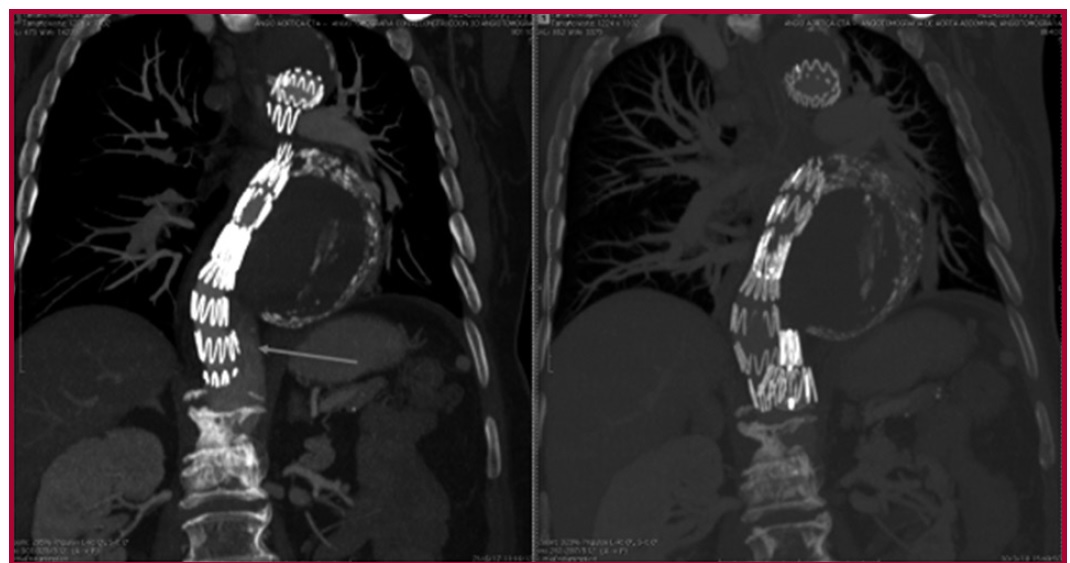

Tratamiento de la disección aórtica crónica complicada mediante la embolización de la falsa luz distal